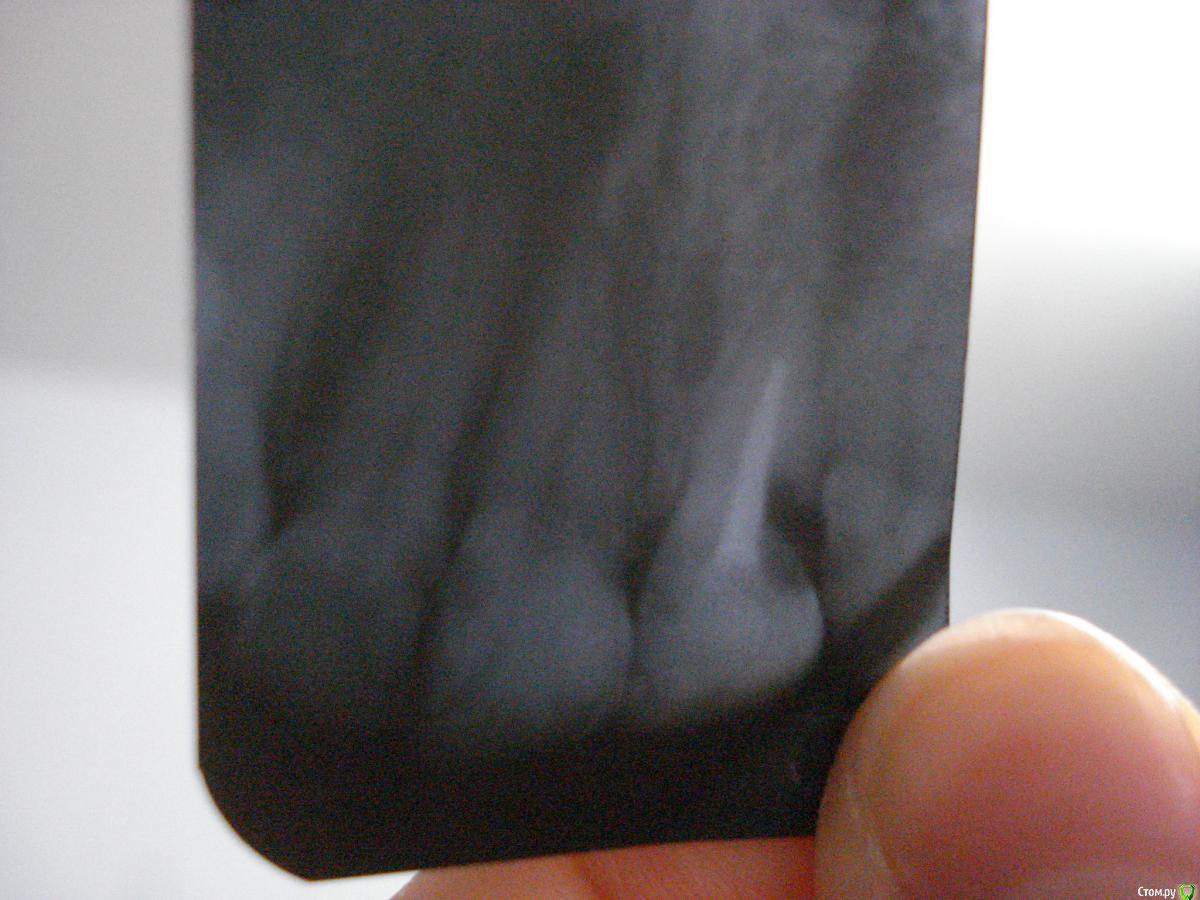

Olga1988 Опубликовано 23 декабря, 2015 Поделиться Опубликовано 23 декабря, 2015 Доброго времени суток! Такая проблема: над единичкой справа появился прыщик (примерно месяца 1,5 назад). Не болит, не увеличивается, только когда в нем скапливается гной - мешает. Зуб мертвый уже давно. На рентгене виден не штифт, а старая пломба (лет 17 назад) в корне. Врачи говорят, что это не свищ и корень в порядке, тогда что это может быть?P.S.: с внутренней стороны зубов кариеса не видно. Ссылка на комментарий

DmitrySH Опубликовано 23 декабря, 2015 Поделиться Опубликовано 23 декабря, 2015 Если судить по снимку, то кариес корня. разрушено все глубоко. Удалять. 6 Ссылка на комментарий

DmitrySH Опубликовано 23 декабря, 2015 Поделиться Опубликовано 23 декабря, 2015 С большой вероятностью, да.На вашем снимке трудно понять текущее состояние соседних зубов, видно только все в пломбах. 1 Ссылка на комментарий

Ker Опубликовано 23 декабря, 2015 Поделиться Опубликовано 23 декабря, 2015 (изменено) Еще по снимку есть кариес между центральными резцами. Изменено 23 декабря, 2015 пользователем Ker Ссылка на комментарий